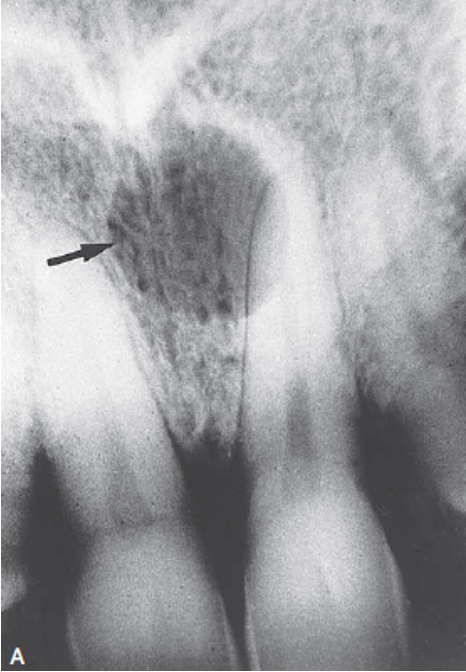

This unilocular radiolucency around the crown of an unerupted second premolar is most likely a

A) normal developmental sac.

B) dentigerous cyst.

C) primordial cyst.

D) lateral periodontal cyst.

A dentigerous cyst is a well-defined unilocular radiolucency around the crown of an unerupted tooth. A normal developmental sac has a much smaller radiolucency around the crown. A primordial cyst develops in place of a tooth. The lateral periodontal cyst is most often seen in the mandibular cuspid and premolar region.